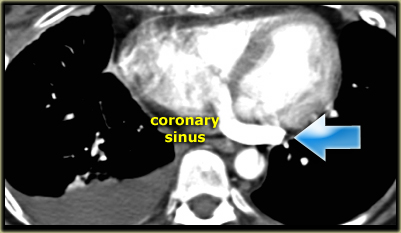

Left Superior Vena Cava

- Represents persistent left common cardinal vein

- Passes anterior to left main bronchus and drains into dilated coronary sinus

- 0.5% of general population and 5% of patients with congenital heart disease

- Small Right SVC in 90% of cases

Describe the images on the left and then continue reading.

On the left side there is a vascular structure, that runs inferiorly below the level of the left hilum and enters into a dilated coronary sinus.

The diagnosis is left or double superior vena cava.